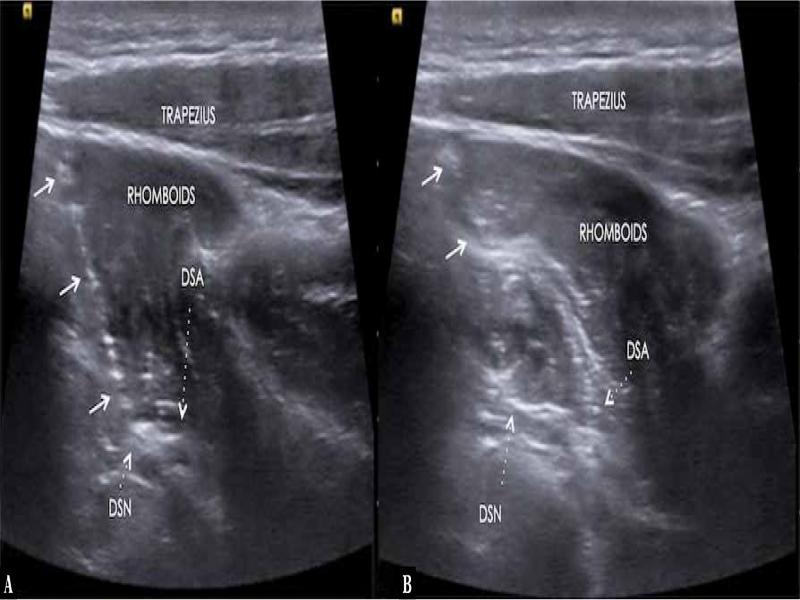

Fig. 2.

Longitudinal ultrasound image showing the needle (arrow) with tip ( A ) adjacent to DSN and injectate adjacent to the DSN ( B )

Siemens Acuson NX3 Elite Ultrasound Machine with 6–15 MHz linear transducer is placed perpendicular to the superomedial border of the scapula. The dorsal scapular artery is identified deep to the rhomboid muscles, parallel and along the medial border of the scapula using power Doppler or colour Doppler. The dorsal scapular artery lies between the serratus posterior and the rhomboid major and minor muscles. The dorsal scapular nerve is identified as a small oval hypoechoic structure just medial to the dorsal scapular artery terminating at the T7 spinous process level. Once the nerve was identified and the site of entrapment was visualised, the needle trajectory used was planned medially to laterally in the plane along the long axis of the probe and using a 22 G spinal needle hydrodissection with a total of 12 ml of injectate (4 ml of 1% lignocaine + 7 ml of 5% dextrose and 1 ml of injection triamcinolone (40 mg) (Fig. 2).